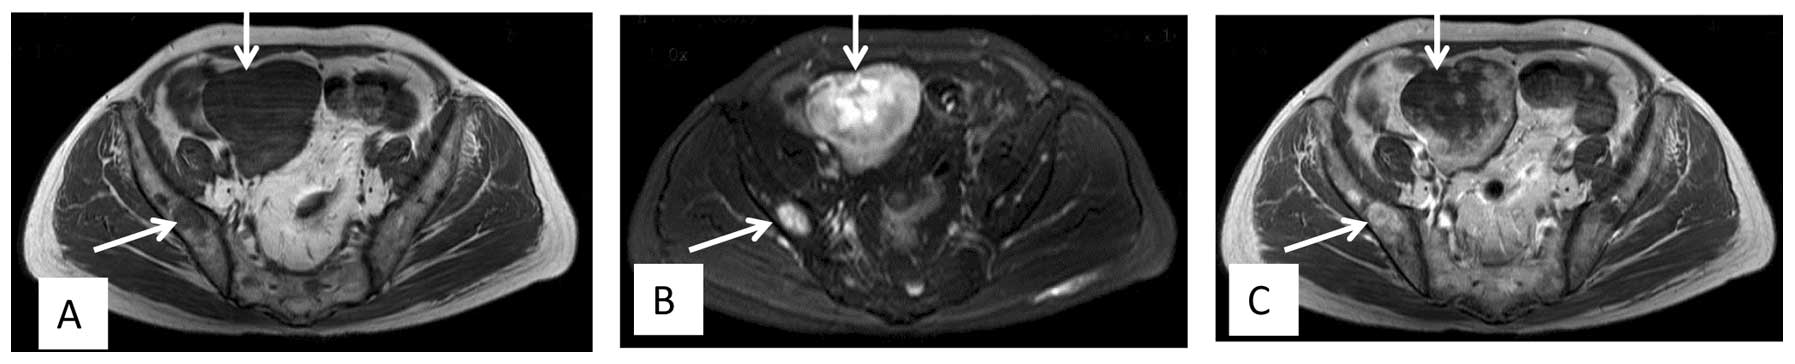

Following recovery from the surgery, radiotherapy was administered at 48 Gy for 24 fractions over 5 weeks. At 1 week after the initiation of radiotherapy, concurrent chemotherapy consisting of gemcitabine (0.8 g/m2 on days 1 and 8) and docetaxel (75 mg/m2 on day 8) was administered. The adverse events were mild, such as leukopenia of World Health Organization grade I (4). At 16 days post-radiotherapy, a second course of chemotherapy with the same regimen was administered. Another 18 days later, computed tomography (CT) detected a 4.5×3.7-cm mass in the abdominal cavity below the gastric body. Several days later, the patient started complaining of blurred vision and painless diplopia in the left eye. Proptosis of the left eye became progressively evident. MRI showed a retrobulbar mass, which was isointense on T1-weighted images and hypo- to isointense on T2-weighted images, with ring enhancement following gadolinium-DTPA infusion (Fig. 2). The mass slightly compressed the optic nerve. The diagnosis was of an orbital metastasis. To alleviate the eye symptoms, the patient received palliative radiotherapy (21 fractions of 51 Gy over 10 weeks) to the retrobulbar mass. During the radiotherapy, the patient developed multiple metastases in regions that included the pelvic cavity, the pelvis femur and the lumbar vertebrae, and progression of the orbital mass was observed (Fig. 3). However, there was no involvement of the lungs. Although the patient received second-line chemotherapy with ifosfamide (1.8 g/m2 on days 1 to 5) and epirubicin (60 mg/m2 on days 1 and 2), the disease progressed and the patient's performance state deteriorated. The patient succumbed to the disease 3 months later.

Figure 3.

Axial magnetic resonance imaging showing a mass lesion producing hypointense signals on (A) T1-weighted imaging and (B) hyperintense signals on T2-weighted imaging, with (C) slight enhancement in the pelvic cavity. Also, the pelvis showed diffuse signal changes.